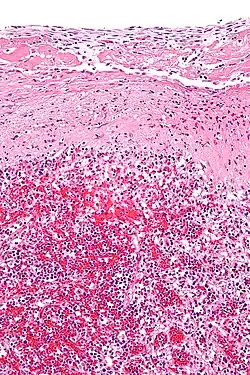

Hyaline cartilage is named after its glassy appearance on fresh gross pathology.[3] On light microscopy of H&E stained slides, the extracellular matrix of hyaline cartilage looks homogeneously pink, and the term "hyaline" is used to describe similarly homogeneously pink material besides the cartilage. Hyaline material is usually acellular and proteinaceous. For example, arterial hyaline is seen in aging, high blood pressure, diabetes mellitus and in association with some drugs (e.g. calcineurin inhibitors). It is bright pink with PAS staining.